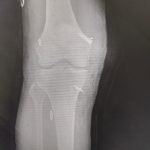

- Robotic Joint Replacement

- Knee Replacement Surgery